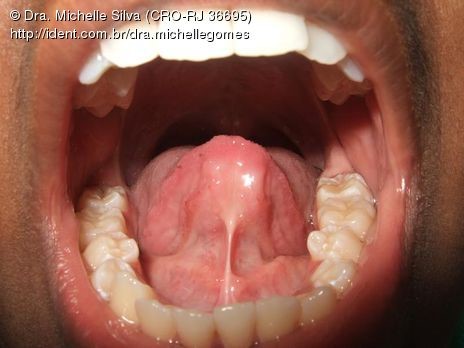

Imagem ilustrativa da posição anatómica normal do freio lingual:

O freio da língua é uma membrana que se posiciona normalmente da metade da face inferior da língua até ao soalho bocal.